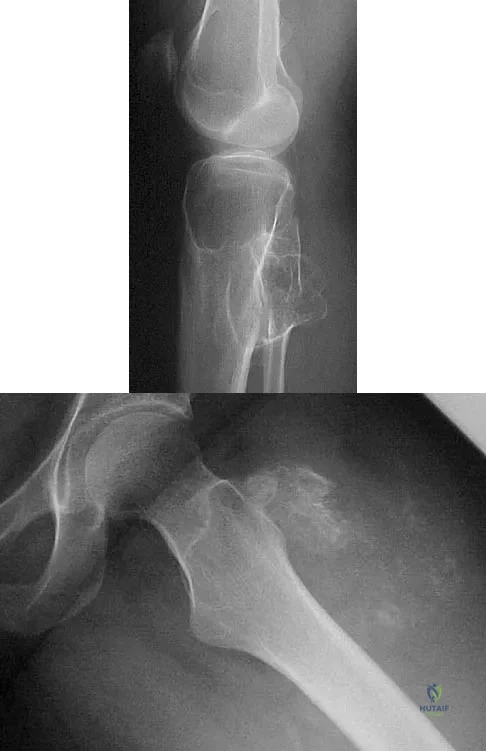

Figures 44a and 44b show the radiographs of a 28-year-old woman who has had progressive hip pain for the past 3 months. What is the most likely diagnosis?

Explanation